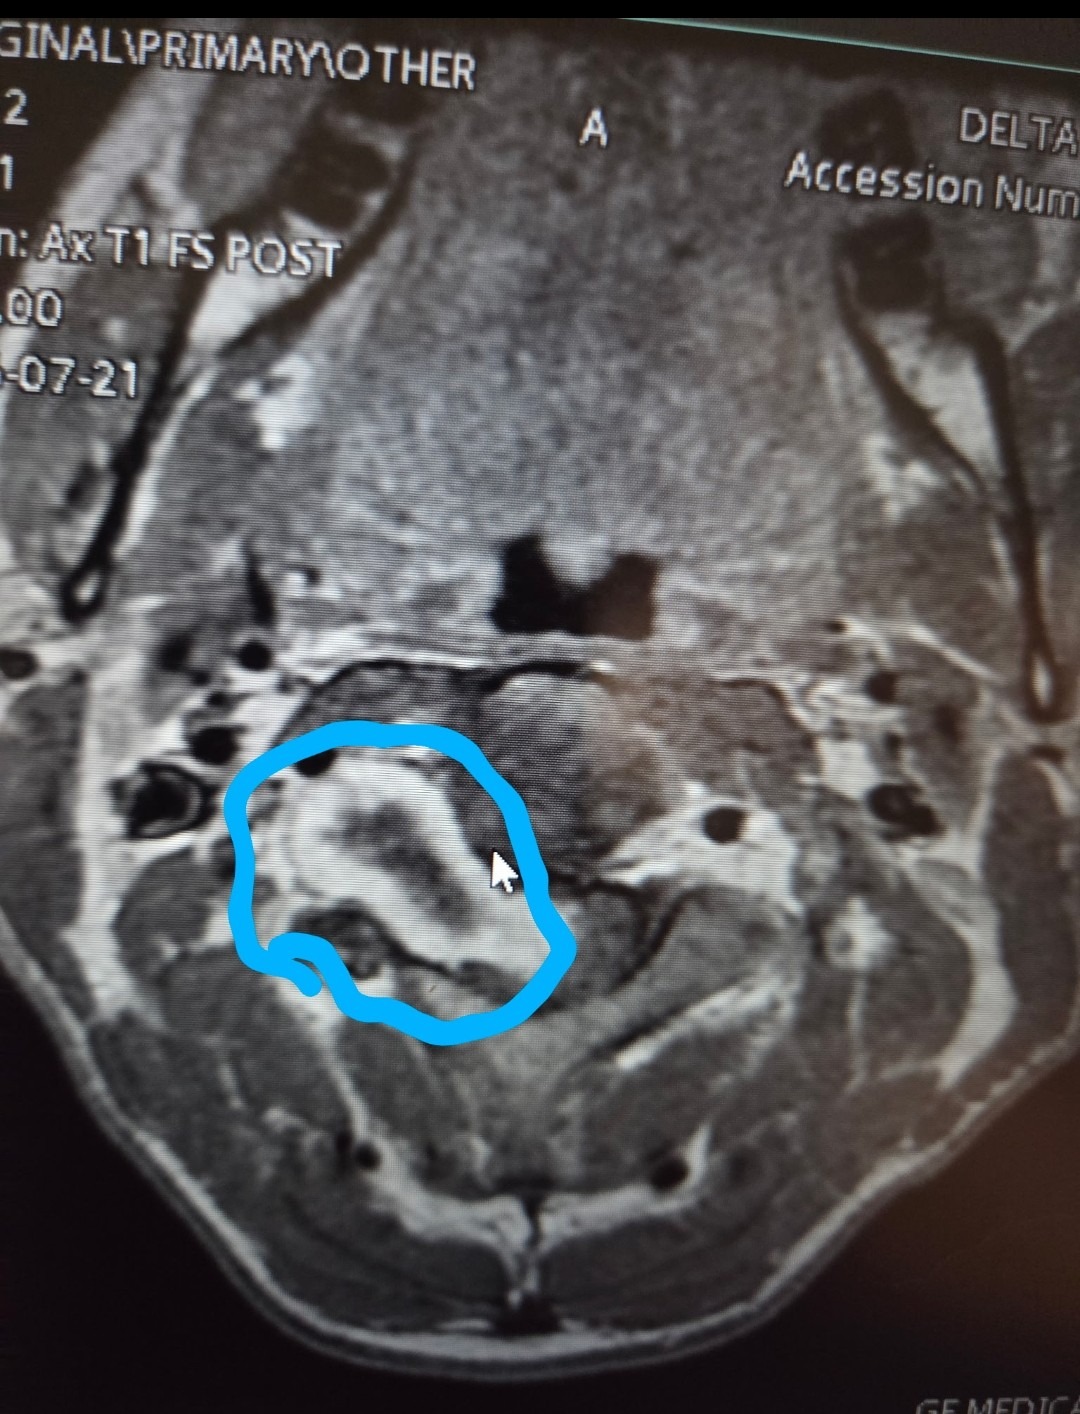

In Augustof 2024, Casey began experiencing severe health issues—intense pain, numbness, migraines, extreme nausea, fatigue, disorientation and many other heath problems. After multiple appointments with different providers, doctors finally discovered a tumor in his neck. The tumor is wrapped around his spinal cord and sensory nerves, causing unbearable pain and numbness affecting his mobility on one side of his body.